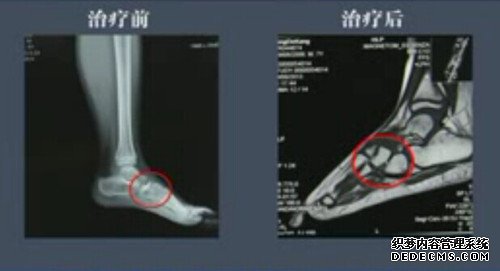

经过详细的检查确诊为左足足舟骨缺血性坏死,左足足底筋膜炎。我院刘文胜院长为其实行了减压植骨术,术后一年多,坏死的地方恢复正常的骨小梁,坏死骨头也恢复到正常位置,走路时疼痛感消失。

一年后小朋友与家人回我院复查,拍片显示已完全恢复,治疗效果堪称“一百分”,患者家属也表示一切都恢复正常,并且感谢刘院长。

患者康复情况对比

患者走路如常人,并能上下蹲